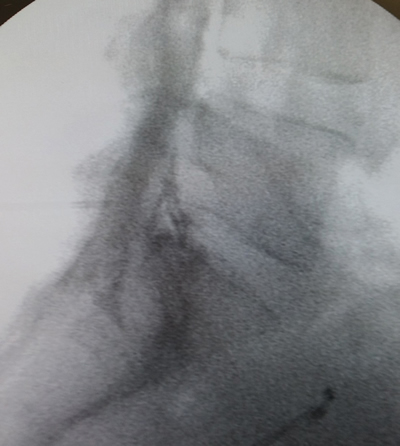

Los procedimientos fueron realizados en sala de operaciones, con anestesia local con lidocaína al 0,5 %, mediante abordaje interlaminar parasagital homolateral al dolor en los espacios L4-L5 o L5-S1, con aguja de Tuohy número 17 o 18, 3½ o 4¾ pulgadas según la complexión física del paciente, con identificación del espacio epidural mediante pérdida de resistencia con suero fisiológico. Se utilizó iopamiron como medio de contraste para visualizar el epidurograma (Figuras 1 y 2).

Fig. 2. Enfoque radiológico lateral de la inyección de contraste en el espacio epidural, durante una inyección epidural de esteroides mediante el abordaje interlaminar parasagital derecho a nivel del espacio L5-S1.